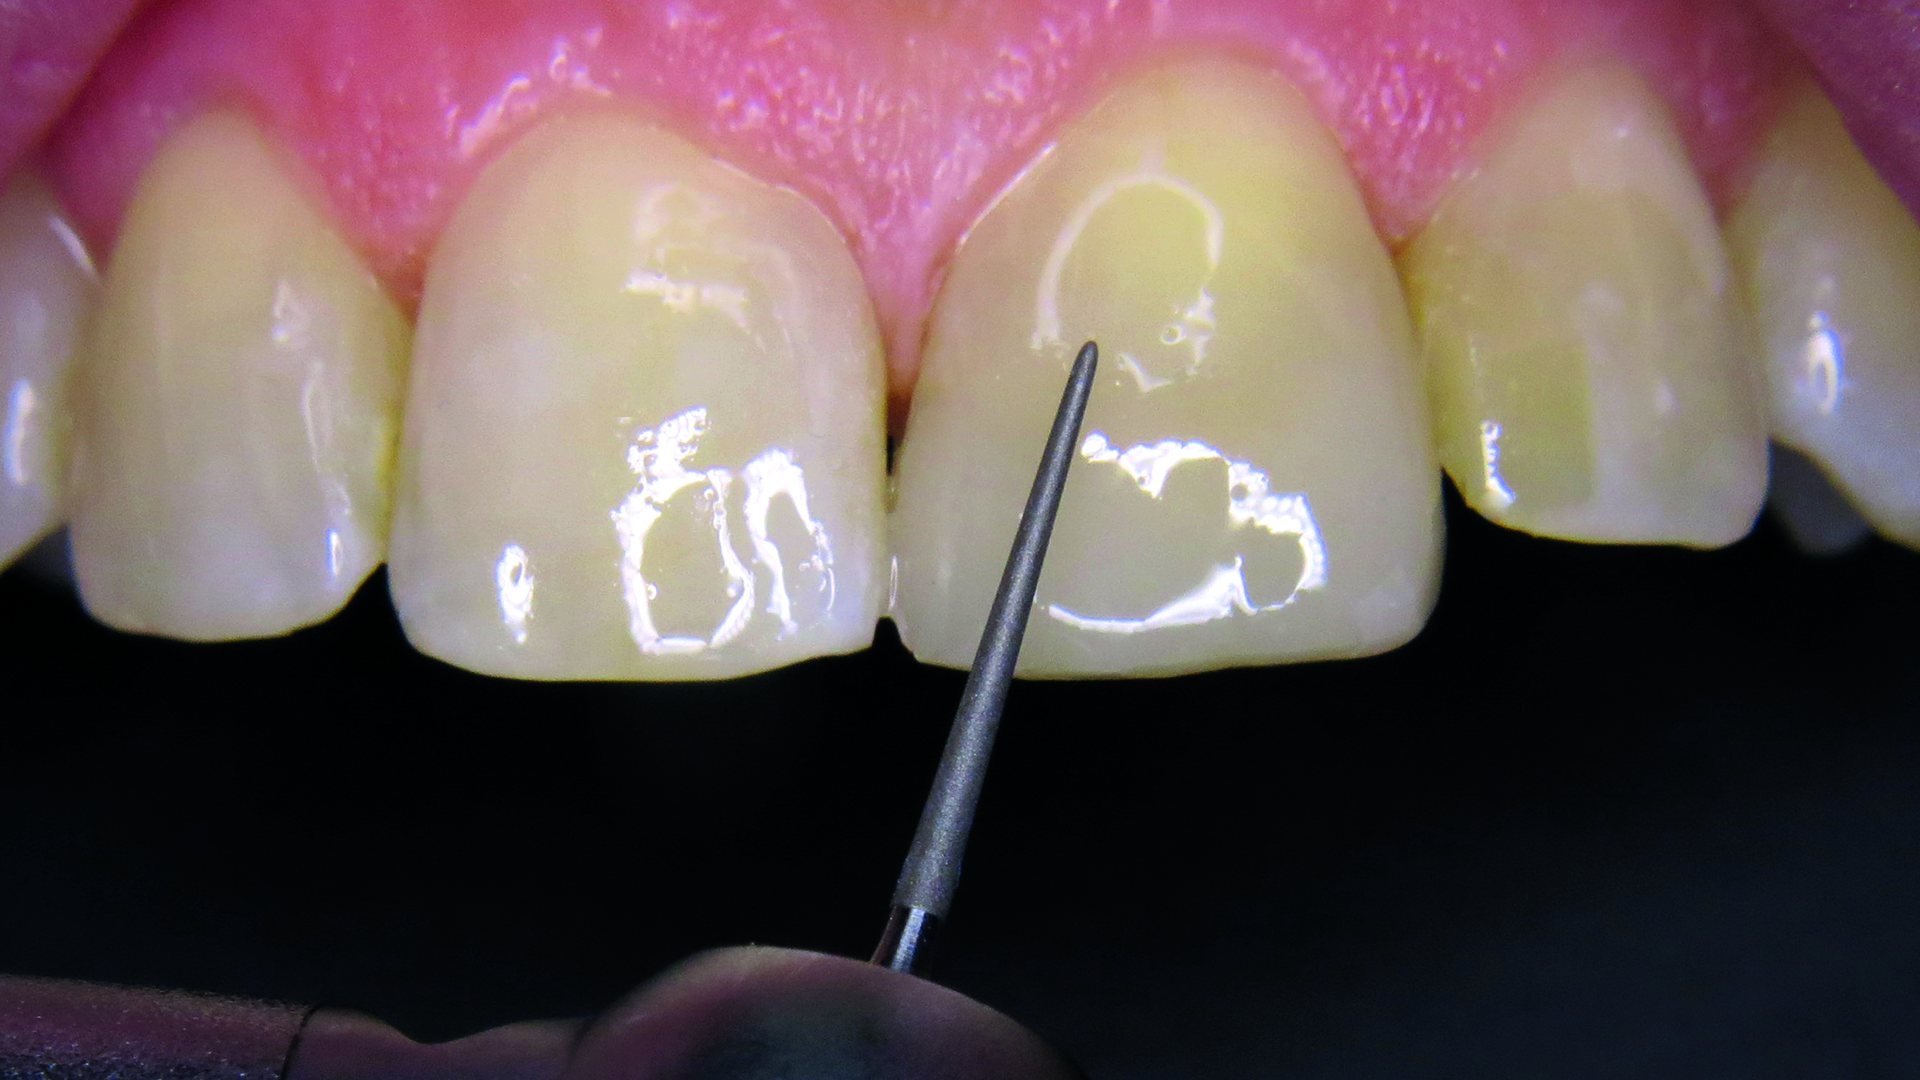

Ząb opracowano zgodnie z zasadami techniki adhezyjnej ze ścięciem pod kątem krawędzi stycznych szkliwa i zapewnieniem ochrony tkanek twardych. Następnie zastosowano technikę całkowitego wytrawiania z zastosowaniem 35% kwasu fosforowego Vococid (VOCO GmbH, Niemcy). Kwas nałożono na powierzchnię szkliwa na ok. 15 sekund (ryc. 5), a następnie na zębinę przez kolejne 15 sekund.

Ryc. 5. Wytrawiacz umieszczony na szkliwie.